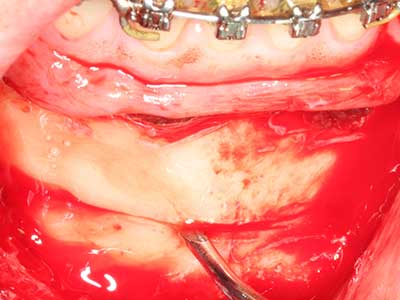

When surgical procedures are performed on bone in the immediate vicinity of sensitive structures such as blood vessels or nerves, rotary instruments pose a significant risk of iatrogenic injury. Piezoelectric devices can be helpful for preparation of bone covers and removal of hard tissue close to nerves, particularly for exposure of nerves after iatrogenic injury but also during nerve lateralization for resective and reconstructive procedures or implant placement (Fig. 17-20). Light contact between the piezotip and the nerve does not generally result in damage but proceeding incautiously with saw-like motions or attachments where a residual bone substrate remains may cause temporary or even permanent nerve damage. However, the risk of damage is considered to be substantially lower than when using saws or milling instruments (Pereira, Gealh et al. 2014).